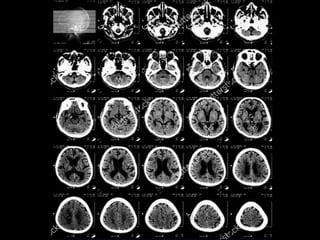

Giải phẫu cắt lớp sọ não

Axial !!!

Giải phẫu cắtlớp sọ não Axial !!!

• 12.